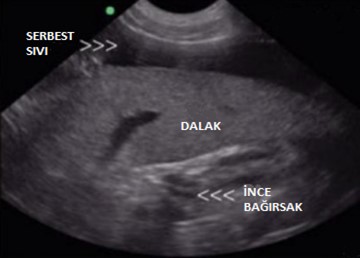

- Ultrason, vücuttaki sıvı dolu ve yumuşak doku organlarının çok daha detaylı bir şekilde bakılmasını sağlar.

- Ultrason, kalp problemlerinin doğru teşhisinde (ekokardiyografi – eko ), lenf düğümlerinin, damarların, troidlerin, karaciğerin, böbreğin, adrenal bezlerin, dalağın, pankreasın, mesanenin, prostatın, rahimin ve bağırsakların değerlendirilmesinde çok önemlidir.

- Ultrason ile bu organların içini görebilir, ultrason kılavuzluğunda aspirasyonlar ve biyopsiler gerçekleştirebilir ve genellikle invaziv keşif cerrahisinden kaçınabiliriz. Ultrason bulgularının nasıl yorumlanacağını bilmek çok önemlidir.